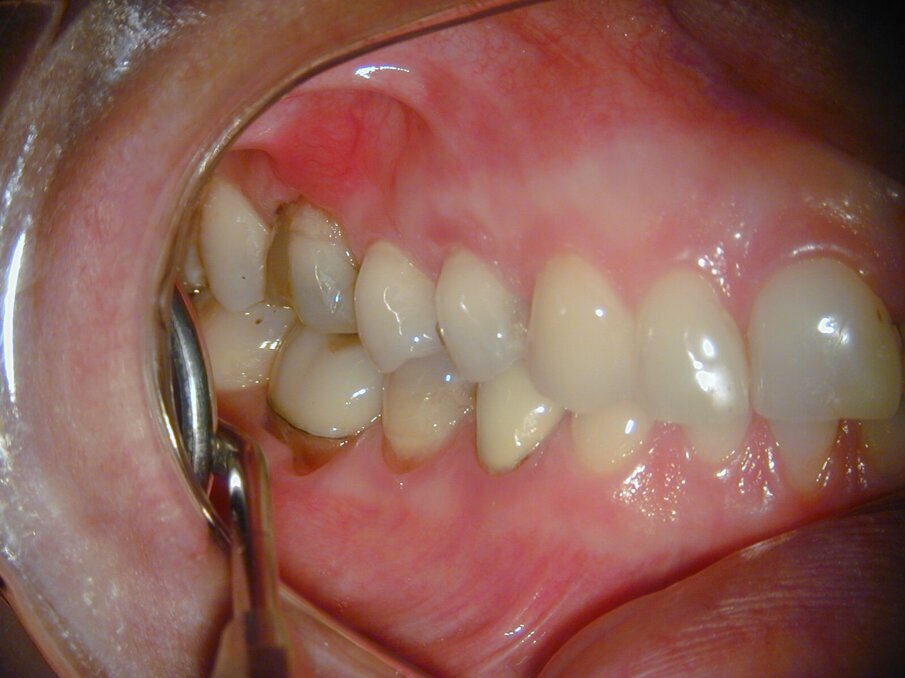

Een 23-jarige vrouw meldde zich bij mij in de praktijk met een pijnklacht aan de 36. Het element was sinds een paar dagen pijnlijk met koud, en intra-oraal onderzoek kon de klachten van de patiënt reproduceren. Röntgenologisch was een diepe amalgaamrestauratie met een para-pulpaire pin zichtbaar (afb. 1). De diagnose luidde een irreversibele pulpitis, en na het toedienen van lokale anesthesie werd het element onder rubberdam gebracht en werd een endo ingezet.

Afb. 1: Bitewing van het tweede en derde kwadrant